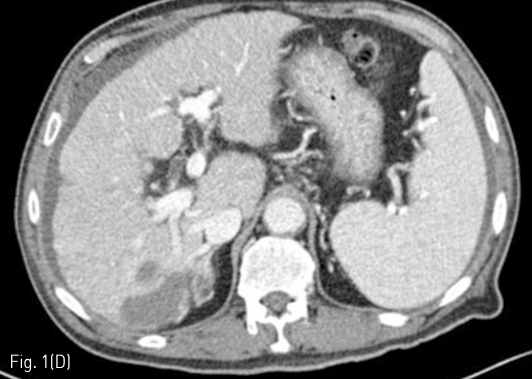

Fig 1D

(C-D) RFA was conducted and follow-up liver CT was performed a month after the treatment. On an arterial phase image, the right posterior portal vein (arrow heads) showed hyperenhancement as much as the adjacent hepatic artery.

정기적 추적검사로 시행한 자기공명영상 (MRI)에서 7번 간분절(S7)에 간담도기에 저신호강도로 보이고 확산강조영상에서 고신호강도로 보이는 간암으로 의심되는 결절이 발견되어 고주파 열치료술이 시행되었다 (Fig. 1A, 1B). 10개월 후 추적검사로 시행한 전산화 단층 촬영의 동맥기 영상에서 우측 후방 간문맥이 주위 간동맥만큼 조영증강이 되는 소견을 보이고 있다(Fig. 1C, 1D). 동맥기 영상에서 간동맥과 간문맥 사이에 연결성이 보여 간동문맥단락이 의심되는 소견을 보이고 있다(Fig. 2).